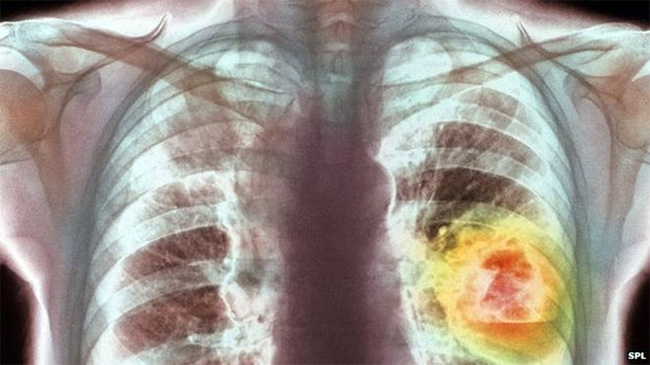

क्यान्सर एक प्रकारको प्राणघातक रोग हो । क्यान्सरबाट पिडित विरामी सपिजलै ठीक हुँदैनन्, किनकी यस रोगको लक्षण ढिला पत्ता लाग्छ । र, संसारमा क्यान्सर रोगको स्थायी उपचार अहिलेसम्म पत्ता लागेको छैन । समय रहँदै यस रोगको उपचार सही तरिकाले नभएको खण्डलाई यसलाई रोक्न मुश्किल हुन्छ ।

शरीरमा हजारौको संख्यामा खराब कोशिका हुन्छन् । प्रत्येक सेकेन्डमा नयाँ कोशिका पैदा हुन्छ र पुरानो खराब कोशिका नष्ट हुन्छन् । तर क्यान्सर भएमा रातो तथा सेतो रक्तकोषिको सन्तुलन विग्रन थाल्छ । र, कोषिकाको विकास अनियन्त्रित रुपमा भएर क्यान्सरको रुपमा परिणत हुन्छ ।